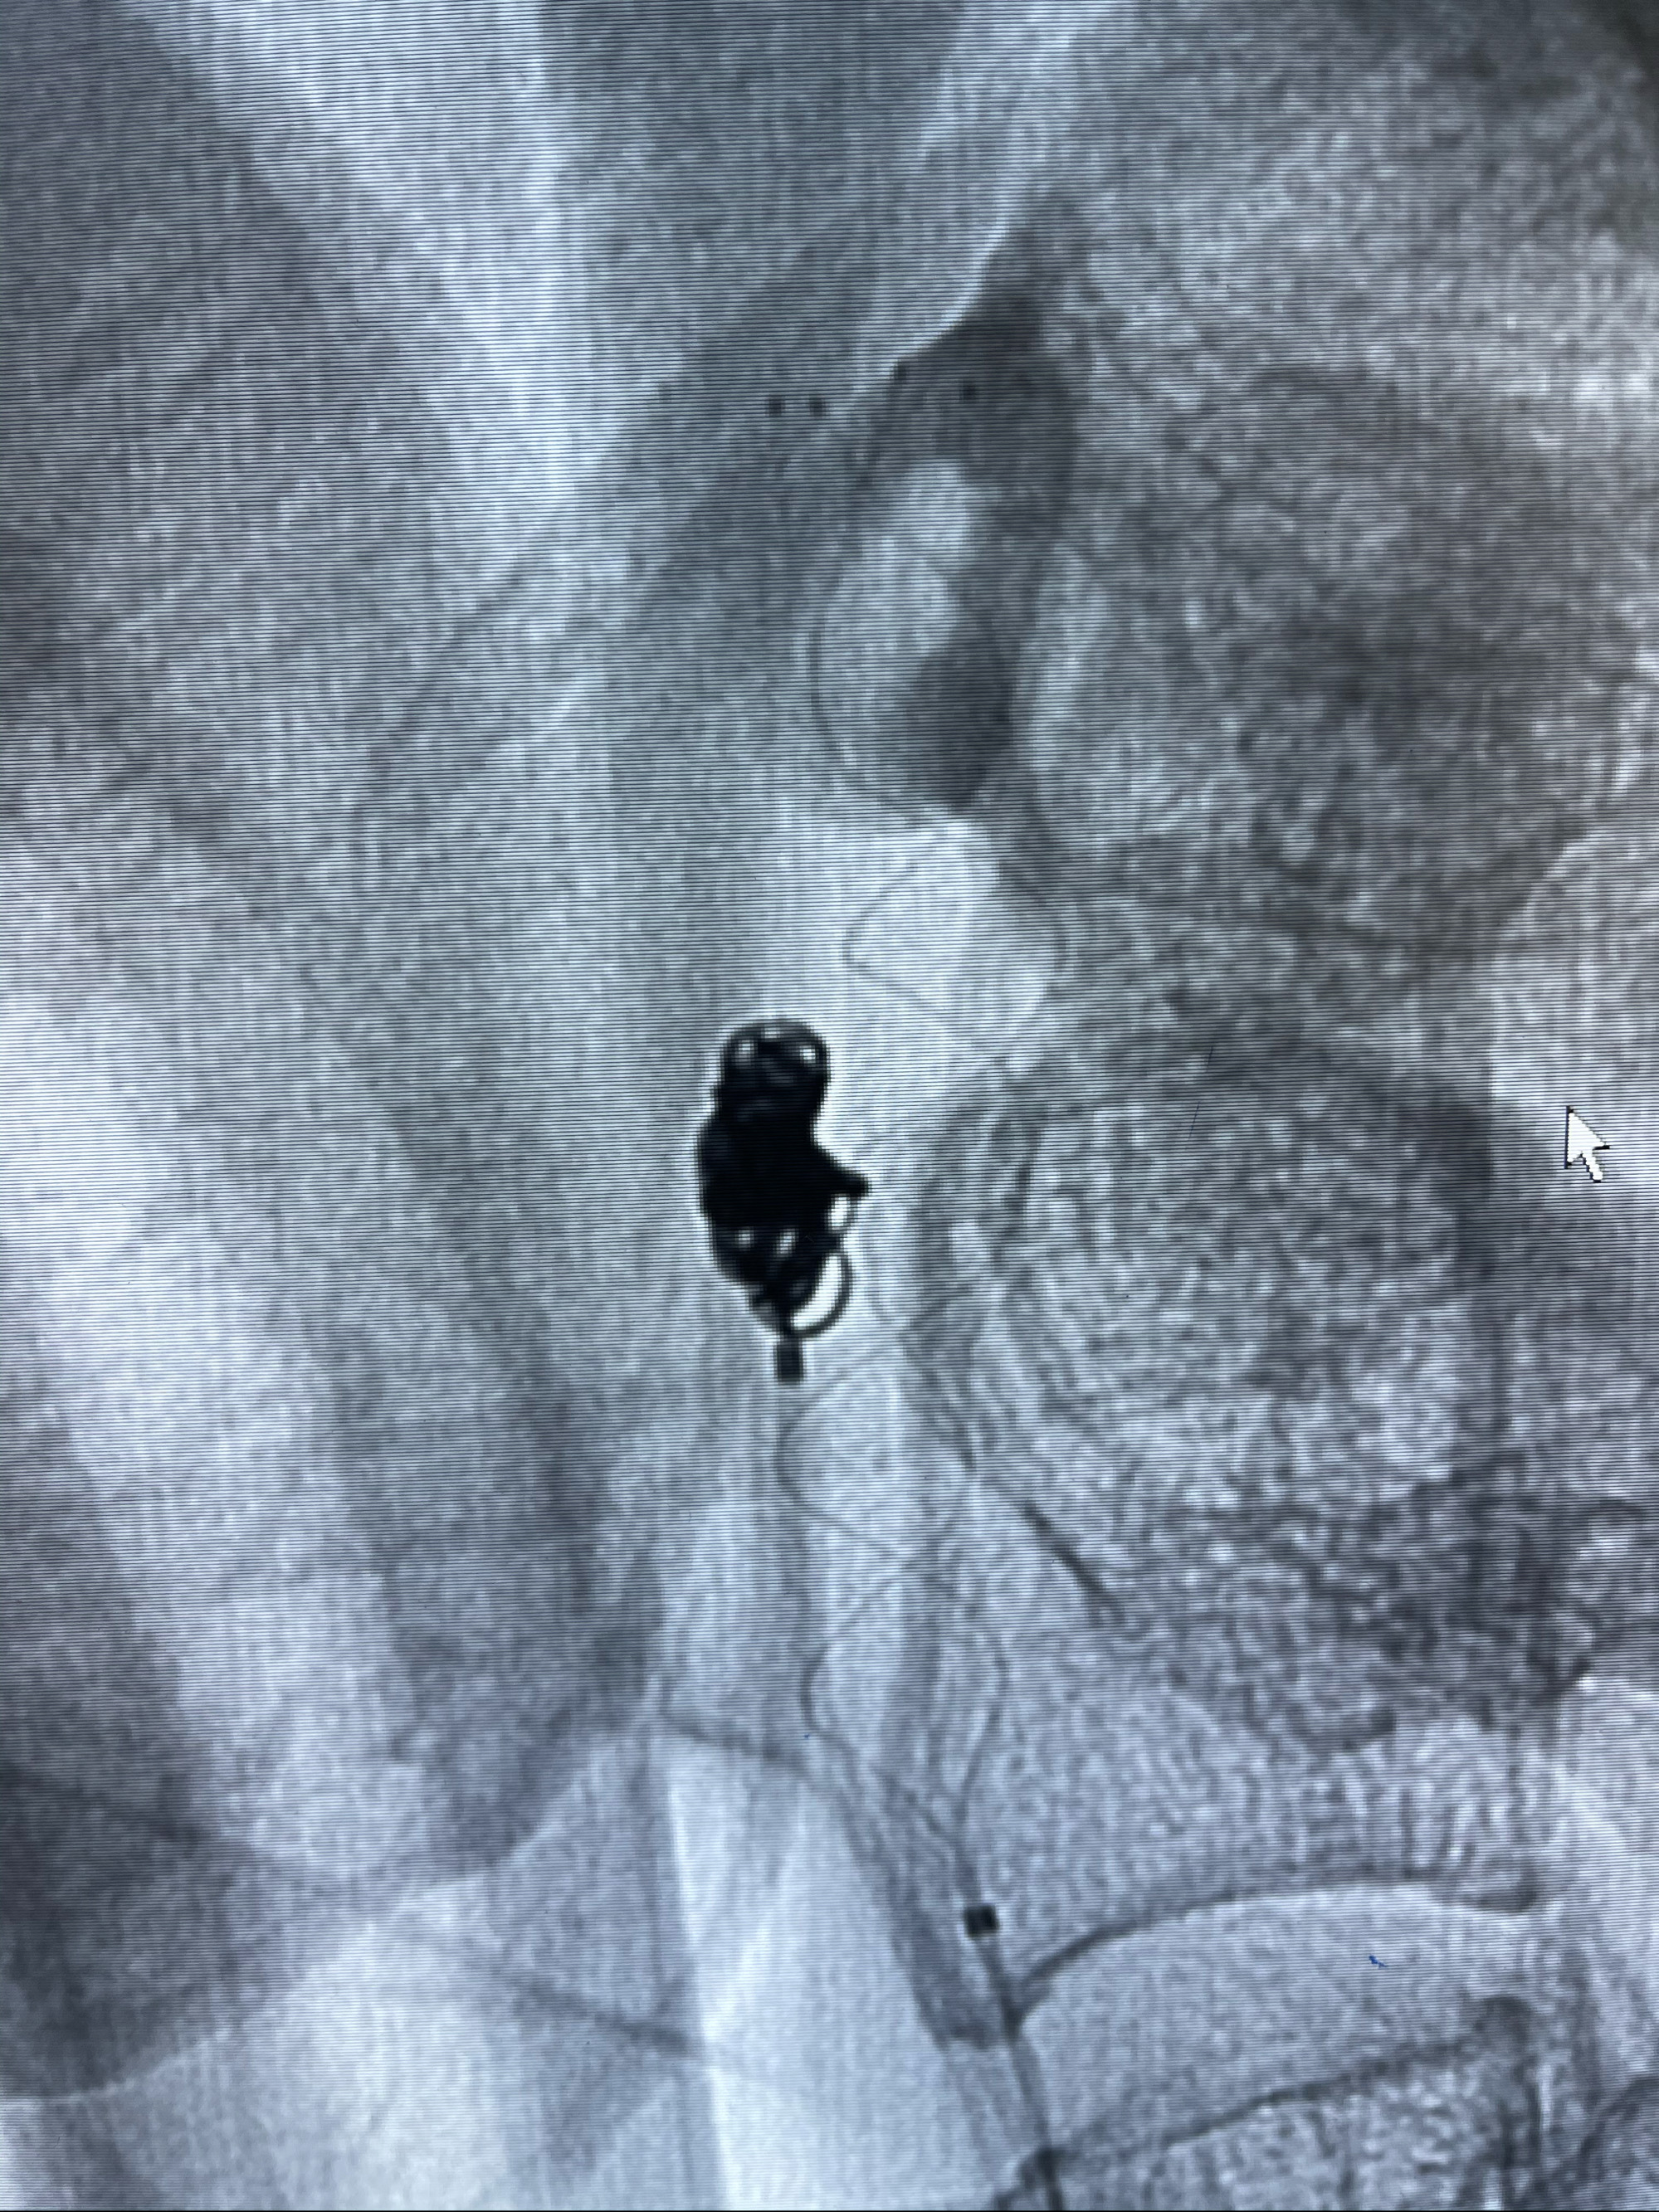

支架释放,透视下

麻醉苏醒佳,遵嘱动作。